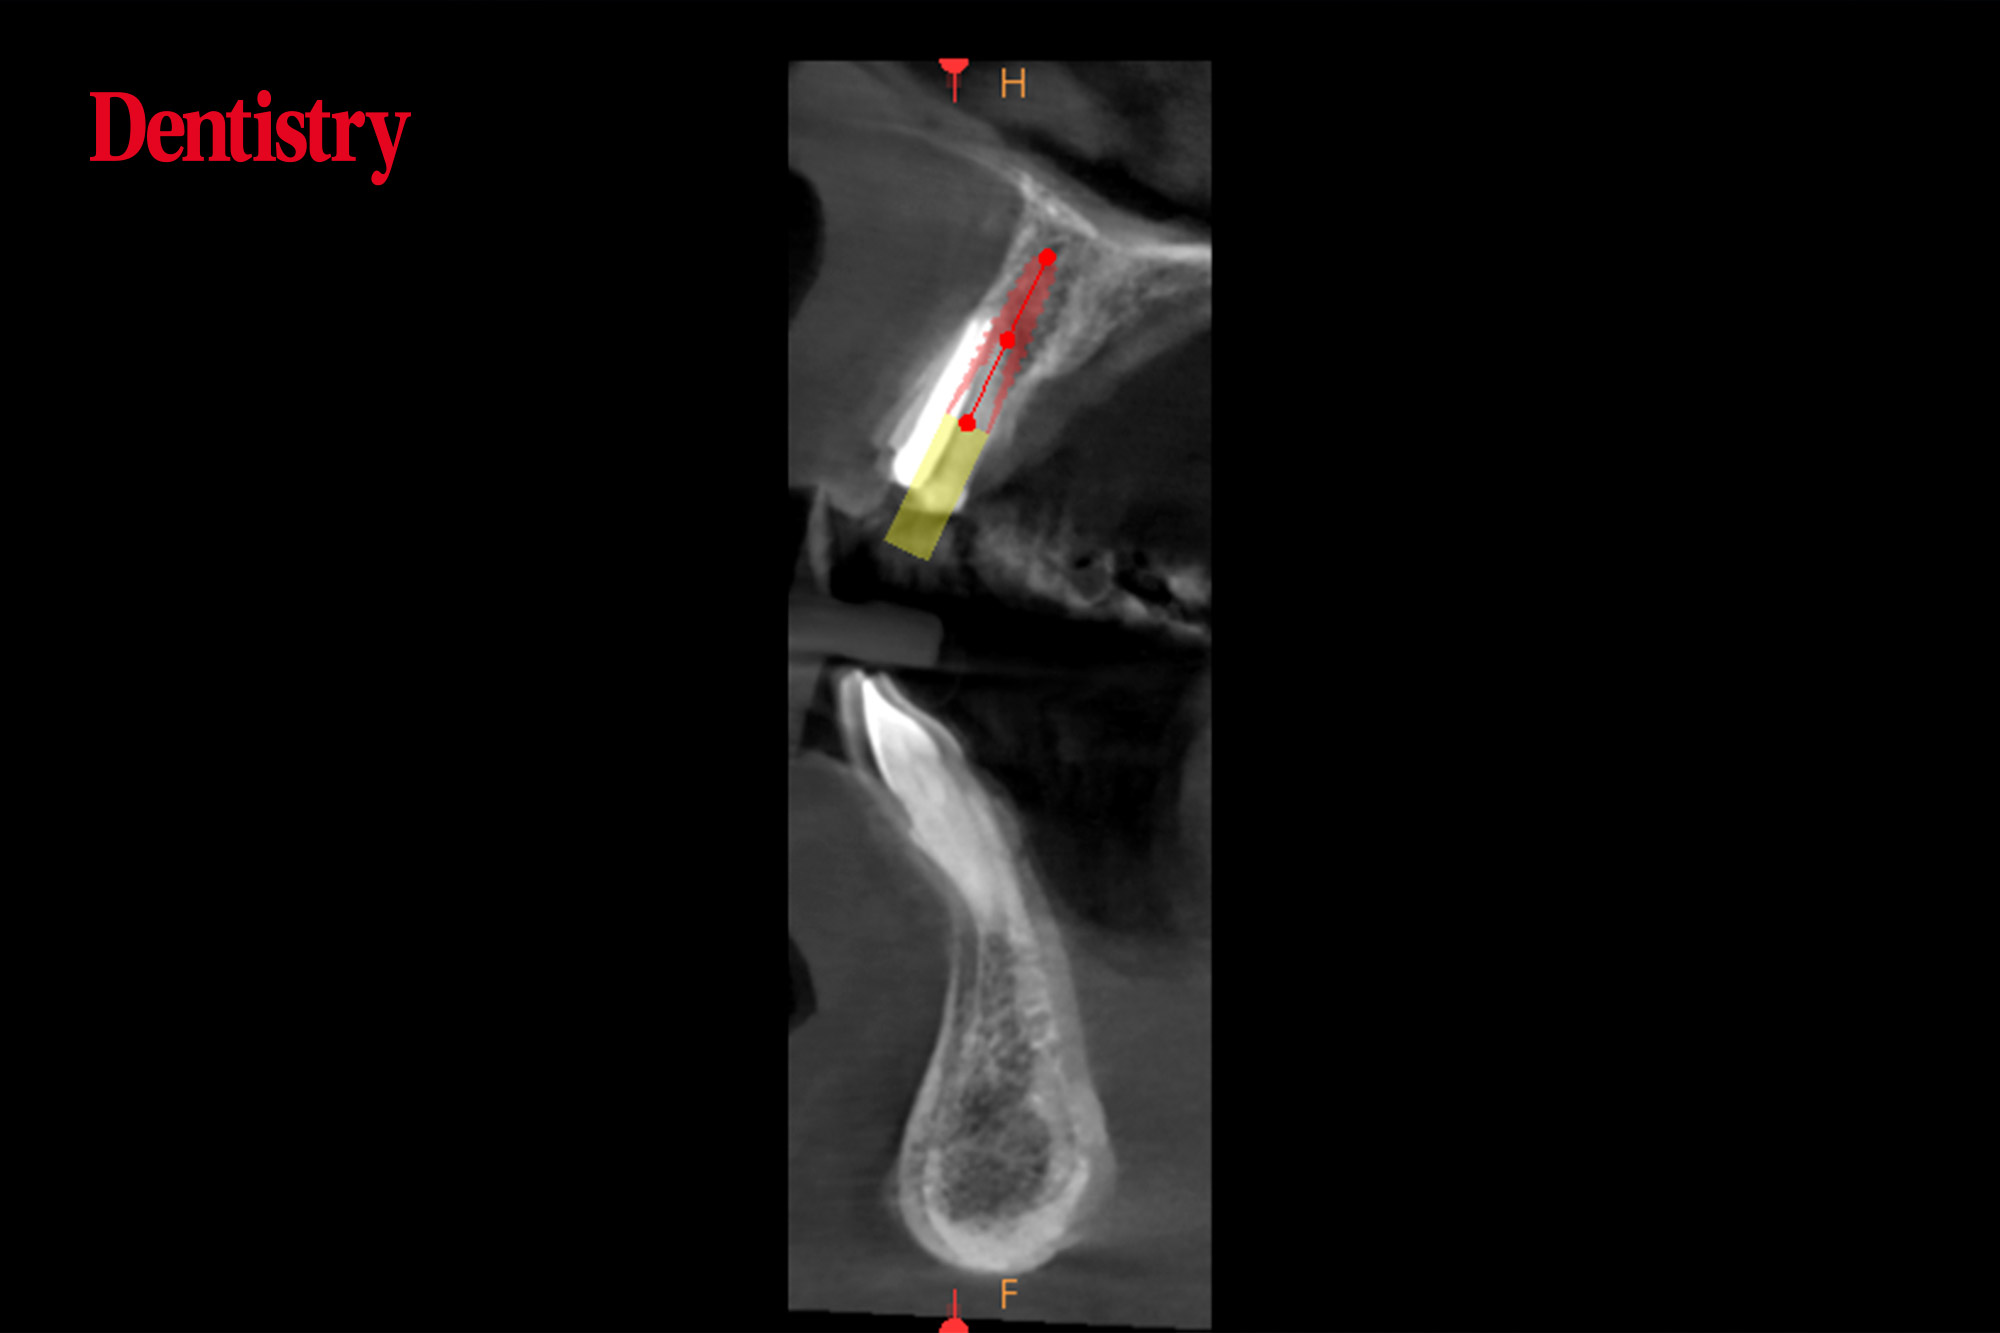

A radiographic assessment using CBCT was completed. This confirmed sufficient apical bone volume for immediate implant placement.

The required guide was designed using Codiagnostix software. This enables the planning of dental implant insertions precisely and easily.

When carrying out immediate implant placement, it is essential to engage the bone palatal and apical to the root. This allows for good primary stability and insertion torque.